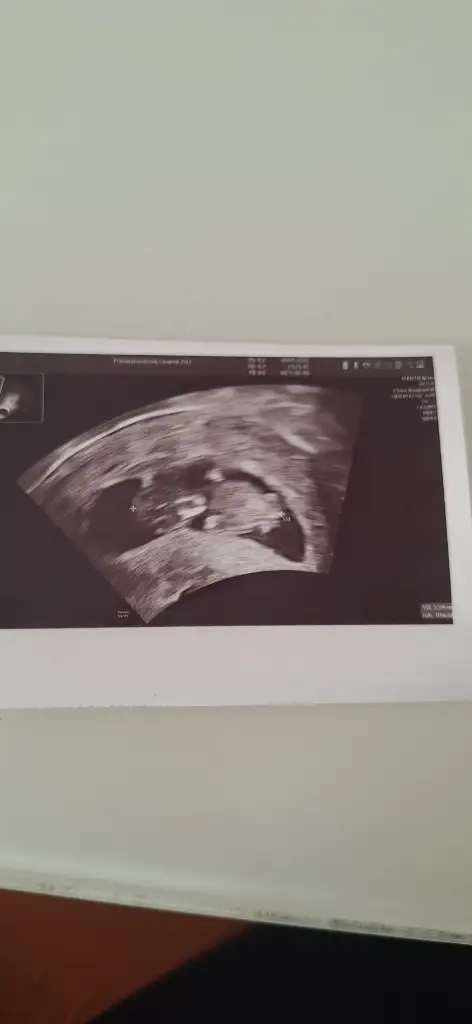

6 haftalik karından ultrasyon tahminde bulunabilir misiniz

5 ve 14. haftaya kadar olan ultrason fotolarınızı paylaşın. Vajinadan mı yoksa karından mı çekildiğini ve kaç haftalık olduğunu da mutlaka belirtin.:anneadayı: